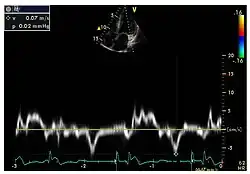

Die linksventrikulären strukturellen Veränderungen des Herzens finden sich bei Morbus-Fabry-Patienten häufig. Mittels Echokardiografie (Ultraschalluntersuchung des Herzens) oder kardialer Magnetresonanztomographie (MRT) können die meist konzentrischen Hypertrophien[80][81] sichtbar gemacht werden. Da mit zunehmendem Alter durch die Ersatzfibrose die linksventrikuläre Hinterwand des Herzens immer dünner wird, ist die Messung der Septumdicke – das ist die Stärke der Scheidewand zwischen linker und rechter Herzhälfte – besonders wichtig. Unabhängig von den strukturellen Veränderungen scheint die Systole, die Phase, in der das Blut aus der linken und rechten Herzkammer herausgepresst wird, bei der Messung mit konventionellen Methoden weitgehend erhalten zu bleiben.[80][81][82][91] Die durch Morbus Fabry verursachte Kardiomyopathie ist durch eine reduzierte Kontraktion und Relaxation des Herzmuskels gekennzeichnet. Gewebedoppler (sowohl tissue velocity imaging als auch strain rate imaging) kann die Herzmuskelfunktion quantifizieren.[7][92] Mit dieser Methode kann die Kardiomyopathie noch vor der Entwicklung einer linksventrikulären Hypertrophie diagnostiziert werden.[91][93]

Gewebedoppler-Echokardiographie des Mitralanulus (Mitralring) mit nahezu normaler systolischer Funktion